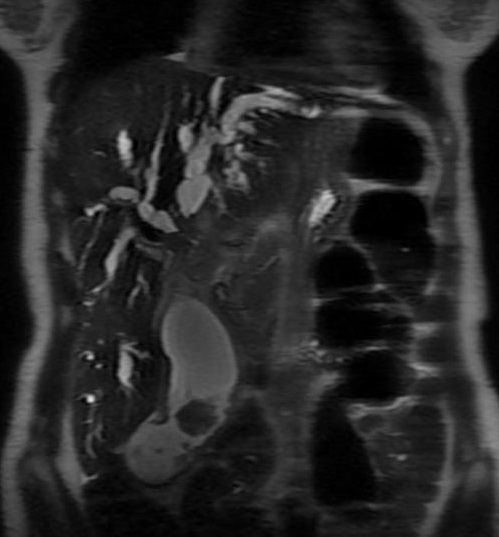

Meme cas en coupe coronale :

La vesicule biliaire est tres distendue avec lesion

en masse de tumeur au fondus . La voie biliaire

intra heaptique est tres dilatee ; Adenocarcinoma

vesiculaire |